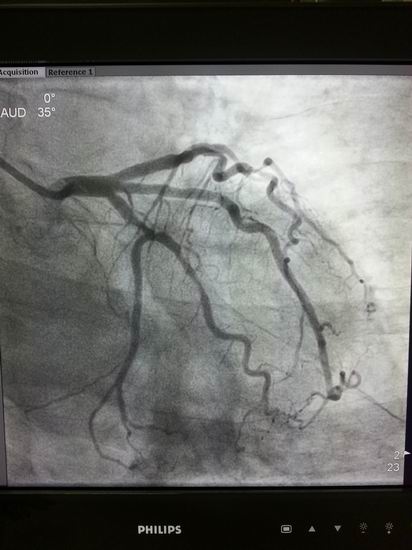

高档数字减影、血管造影系统 Allura Xper FD20

名称:高档数字减影、血管造影系统 Allura Xper FD20

主要功能:采用大平板科技,结合2K影像链,提供极佳图像细节解析能力,1250mA成像能力与“透心凉”高散热球管,“Refresh light”技术消除动态采集时的鬼影,图像质量更高。